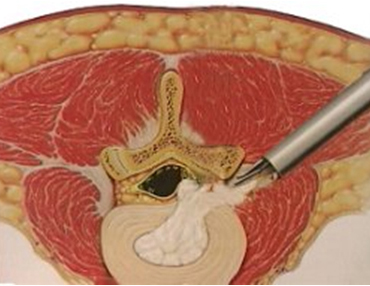

χαμηλÜ βρßσκονται στην σπονδυλικÞ στÞλη. ΕιδικÜ στα επßπεδα Ο4-Ο5

και Ο5-Ι1 εκεß που βρßσκονται και οι πιο πολλÝς κÞλες εßναι τüσο

μεγÜλα, üτι υπÜρχει χþρο για Ýνα εργαλεßο διαμÝτρου 8χιλ. περßπου

διπλÜ απü το νεýρο. ¸τσι γεννÞθηκε πριν απü αρκετÜ χρüνια η ιδÝα για

Το ενδοσκüπιο με Ýνα εργαλεßο

ΑυτÞ η ενδοσκοπικÞ

αφαßρεση κÞλης του μεσοσπονδυλßου δßσκου στην οσφυúκÞ μοßρα (την

μÝση) εßναι μια στην ΕλλÜδα σχεδþν Üγνωστη τεχνικÞ. Ο ασθενεßς Ýχει

μüνο μια ελÜχιστη τομÞ στο δÝρμα (6-8χιλ.) 10 εκ διπλÜ απü την